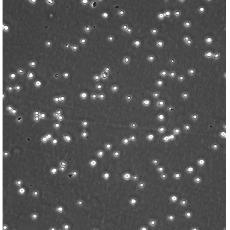

生長特性 suspension

形態(tài)特征 lymphoblast

細(xì)胞描述 CEM/C1是人T細(xì)胞白血病細(xì)胞株CCRF-CEM(見ATCC CCL-119)具有喜樹堿抗性的衍生株。1991年細(xì)胞株選擇并亞克隆了對CPT的抗性。細(xì)胞表現(xiàn)出對CPT類似物水溶性的托泊替康和非水溶性的9-氨基-CPT及10,11-亞甲二氧基-CPT具有交叉抗性。CEM/C1細(xì)胞對CPT的敏感性較母系CEM細(xì)胞低31倍。CEM/C1細(xì)胞表現(xiàn)非典型的多藥抗性和轉(zhuǎn)換拓補(bǔ)異構(gòu)酶I催化活性。對CPT的抗性維持6個(gè)月以上。